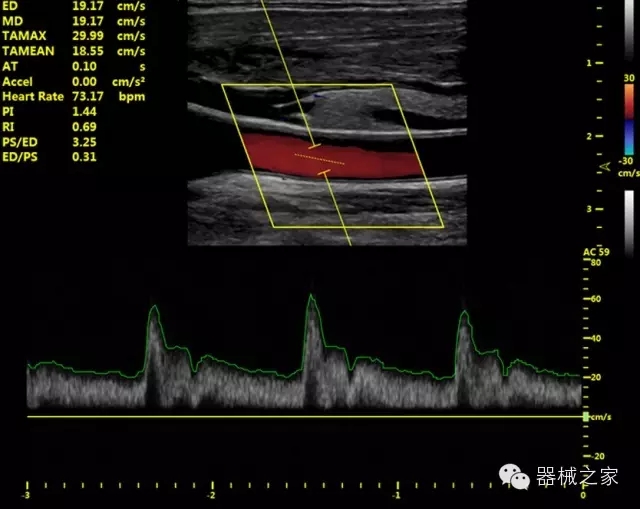

臨床圖片賞析

產(chǎn)品特點

優(yōu)異的成像技術(shù)

·亞陣元技術(shù):獨有的亞陣元技術(shù),對獨立晶片做二次切割,減少旁瓣偽像,增加臨床診斷的準(zhǔn)確性;

·μ-Scan微米成像技術(shù):開立獨有的μ-Scan技術(shù),還原出真實細(xì)膩、層次對比優(yōu)異的二維圖像;

·倒相諧波成像技術(shù):倒相諧波技術(shù)在去除基波信號的基礎(chǔ)上獲取兩倍二次諧波信號,提高組織圖像的對比分辨力;

·智能微血流成像技術(shù):智能微血流捕捉技術(shù)可以提取出隱藏在背景噪聲中的弱血流信號,大大提高低速血流的敏感性;

全面的臨床解決方案

超聲科常規(guī)領(lǐng)域應(yīng)用

·移植S40高端臺式彩超高端平臺技術(shù),滿足超聲科腹部、淺表、婦產(chǎn)科、心血管、肌骨等應(yīng)用,提供超聲科完美解決方案;

·實時的彈性成像技術(shù):提高了小器管(乳腺,甲狀腺、淺表軟組織腫瘤等)疾病鑒別診斷;

·IMT血管內(nèi)中膜自動測量:為血管性疾病評估提供了有效的評估手段;

·心功能綜合指數(shù)(TEI指數(shù)):用于左、右心室整體心臟收縮舒張功能評估的測量方法;

·全方位可調(diào)M型:有利于更好的觀察心腔大小及室壁階段性運動的異常情況;

·組織多普勒成像(TDI):TDI可定量評價心肌運動,判斷是否有局部病變,還可評價早期的舒張功能;

·高效3D/4D成像技術(shù):高速的4D幀頻,豐富的3D成像模式,智能斷層切片功能;

POC領(lǐng)域解決方案

·外觀小巧;

·穿刺增強(qiáng)技術(shù):可有效提高進(jìn)針區(qū)圖像分辨率,提高進(jìn)針亮度,全面提高一次性穿刺的成功率;

全面的術(shù)中探頭解決方案

·小凸探頭:開放性手術(shù),實時監(jiān)測病灶位置,提高手術(shù)成功率,可應(yīng)用于麻醉科、肝膽外科、腫瘤外科、神經(jīng)外科、泌尿外科等手術(shù);

·L型線陣探頭:高分辨率圖像,清晰顯示病灶位置,提高手術(shù)成功率,可應(yīng)用于麻醉科、胸外科、肝膽外科、腫瘤外科、神經(jīng)外科、泌尿外科等應(yīng)用;

·MPTEE:經(jīng)食道探頭術(shù)中監(jiān)測,可測量心臟前負(fù)荷(左室舒張末期大小、右房大?。?、心排血量、后負(fù)荷、收縮功能、室壁運動分析、肝靜脈血流(與中心靜脈壓相關(guān))等,術(shù)后還能及時評估手術(shù)效果評估;

·獨有的大角度及實時溫控技術(shù),能同一切面顯示宮頸及宮體,有效減低了患者的痛苦,及保護(hù)粘膜保證了醫(yī)療安全;

高效的人機(jī)工程學(xué)設(shè)計

·15‘’高清醫(yī)用顯示器;

·內(nèi)置雙探頭接口;

·可升降臺車,1拖3探頭擴(kuò)展器;

·m-Tuning一鍵優(yōu)化;

·粵食藥監(jiān)械(準(zhǔn))字20132230491